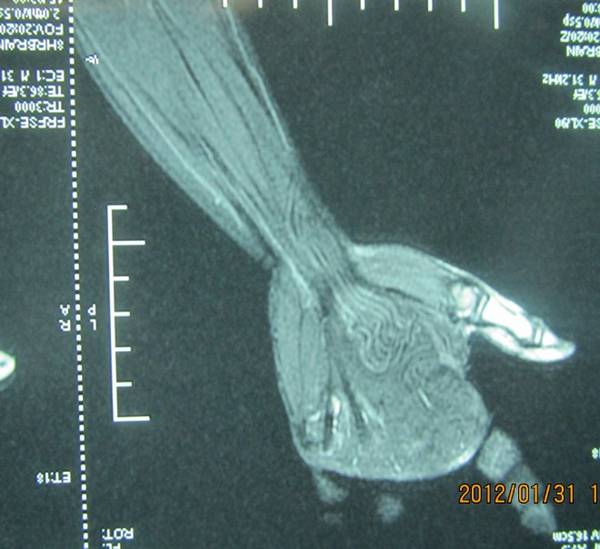

昨天手术一名神经纤维瘤病的患者。

术中电刺激定位鱼际肌的肌支后,就可以保留功能性神经束,大胆切除异常生长的脂肪、神经束膜及外膜。